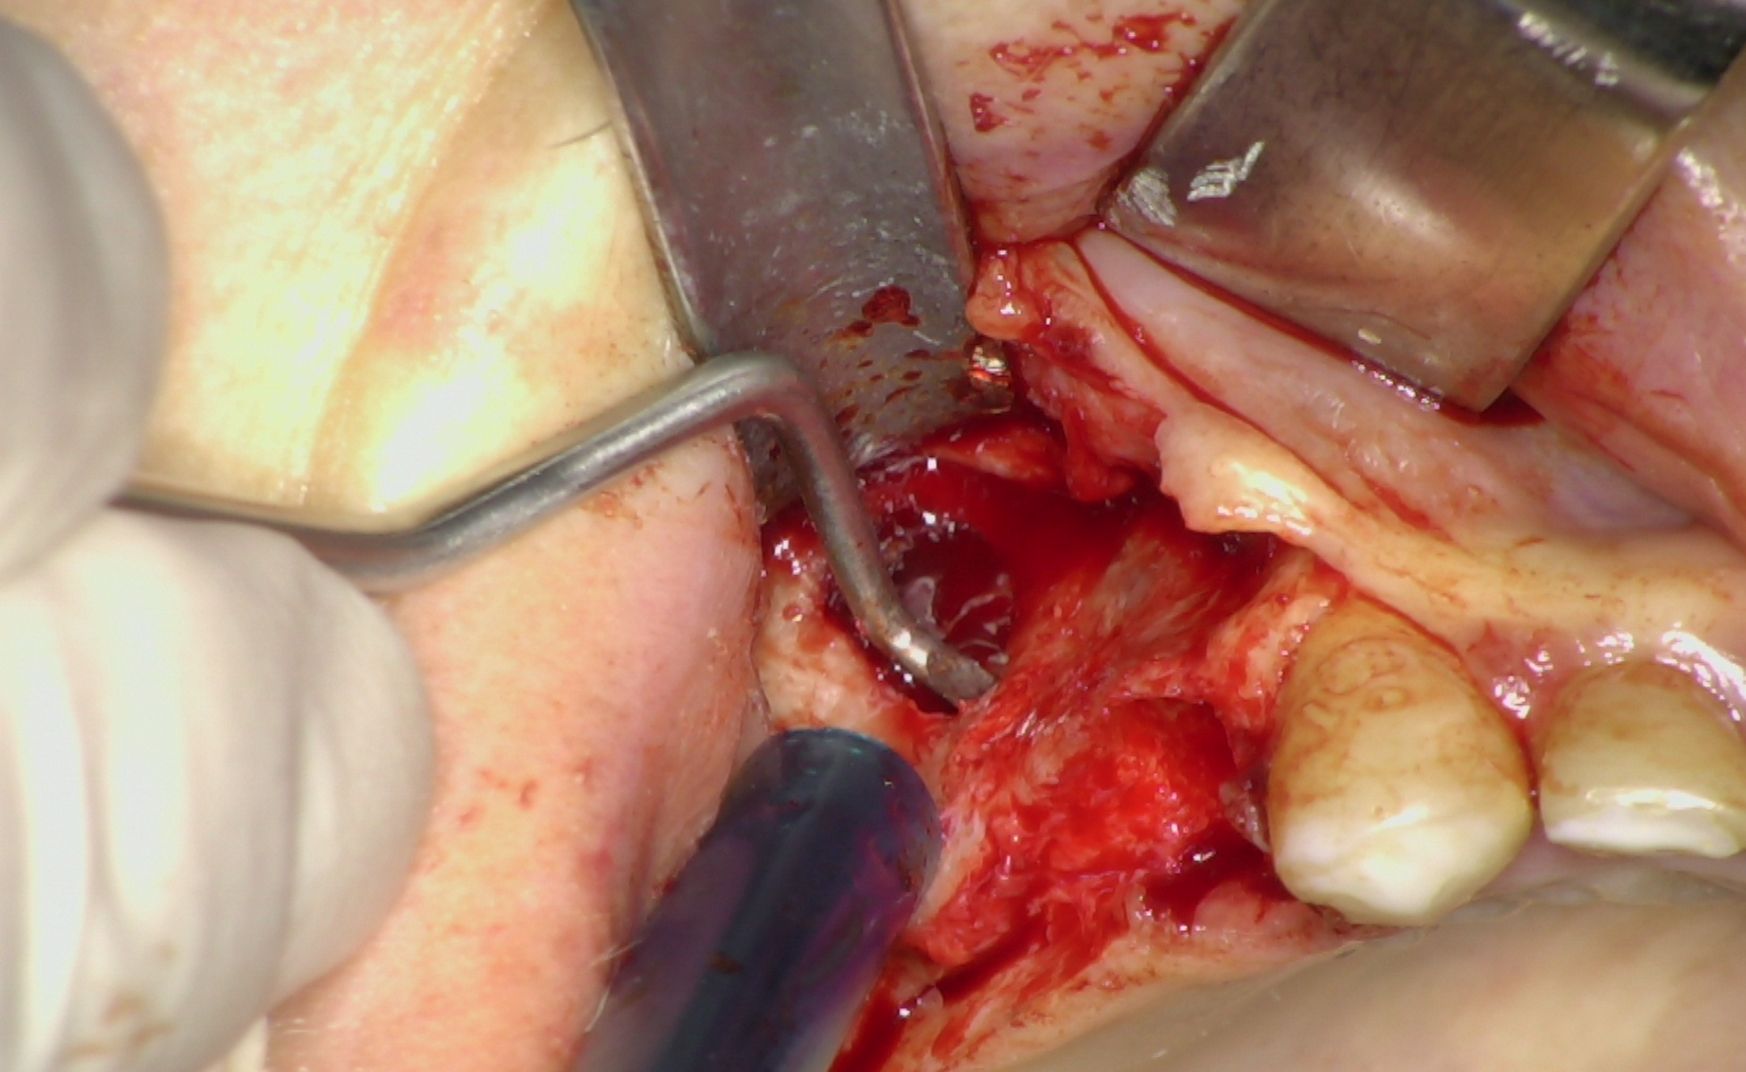

Al termine della fase implantare è stata eseguita una rigenerazione ossea localizzata intorno agli impianti posteriori utilizzando osso autologo prelevato mediante bone scraper (Fig. 5). Questo passaggio ha consentito di colmare eventuali spazi peri-implantari, favorendo i processi di osteointegrazione e contribuendo a migliorare la prognosi a lungo termine.

L'intervento è stato completato in un'unica seduta chirurgica, adottando un approccio minimamente invasivo e nel pieno rispetto dei tessuti. Le immagini intraoperatorie illustrano chiaramente le principali fasi del trattamento: il posizionamento degli impianti anteriori IS+, l'inserimento transinusale degli impianti BT-Rhyno e l'applicazione di osso autologo per la rigenerazione finale (Fig. 6).